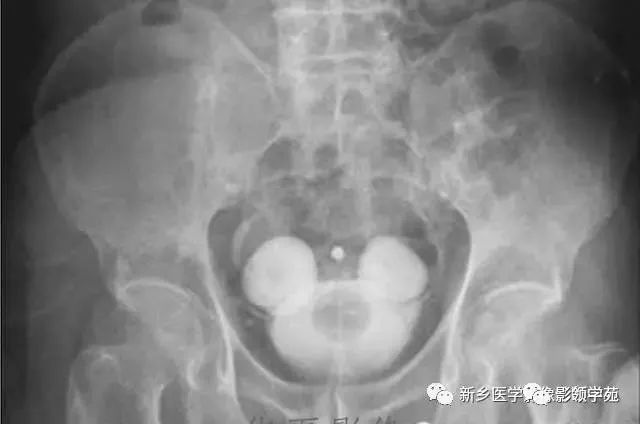

盆腔dr正位片示膀胱结石.

惊奇600多颗结石堵在膀胱活人差点真的被尿憋死